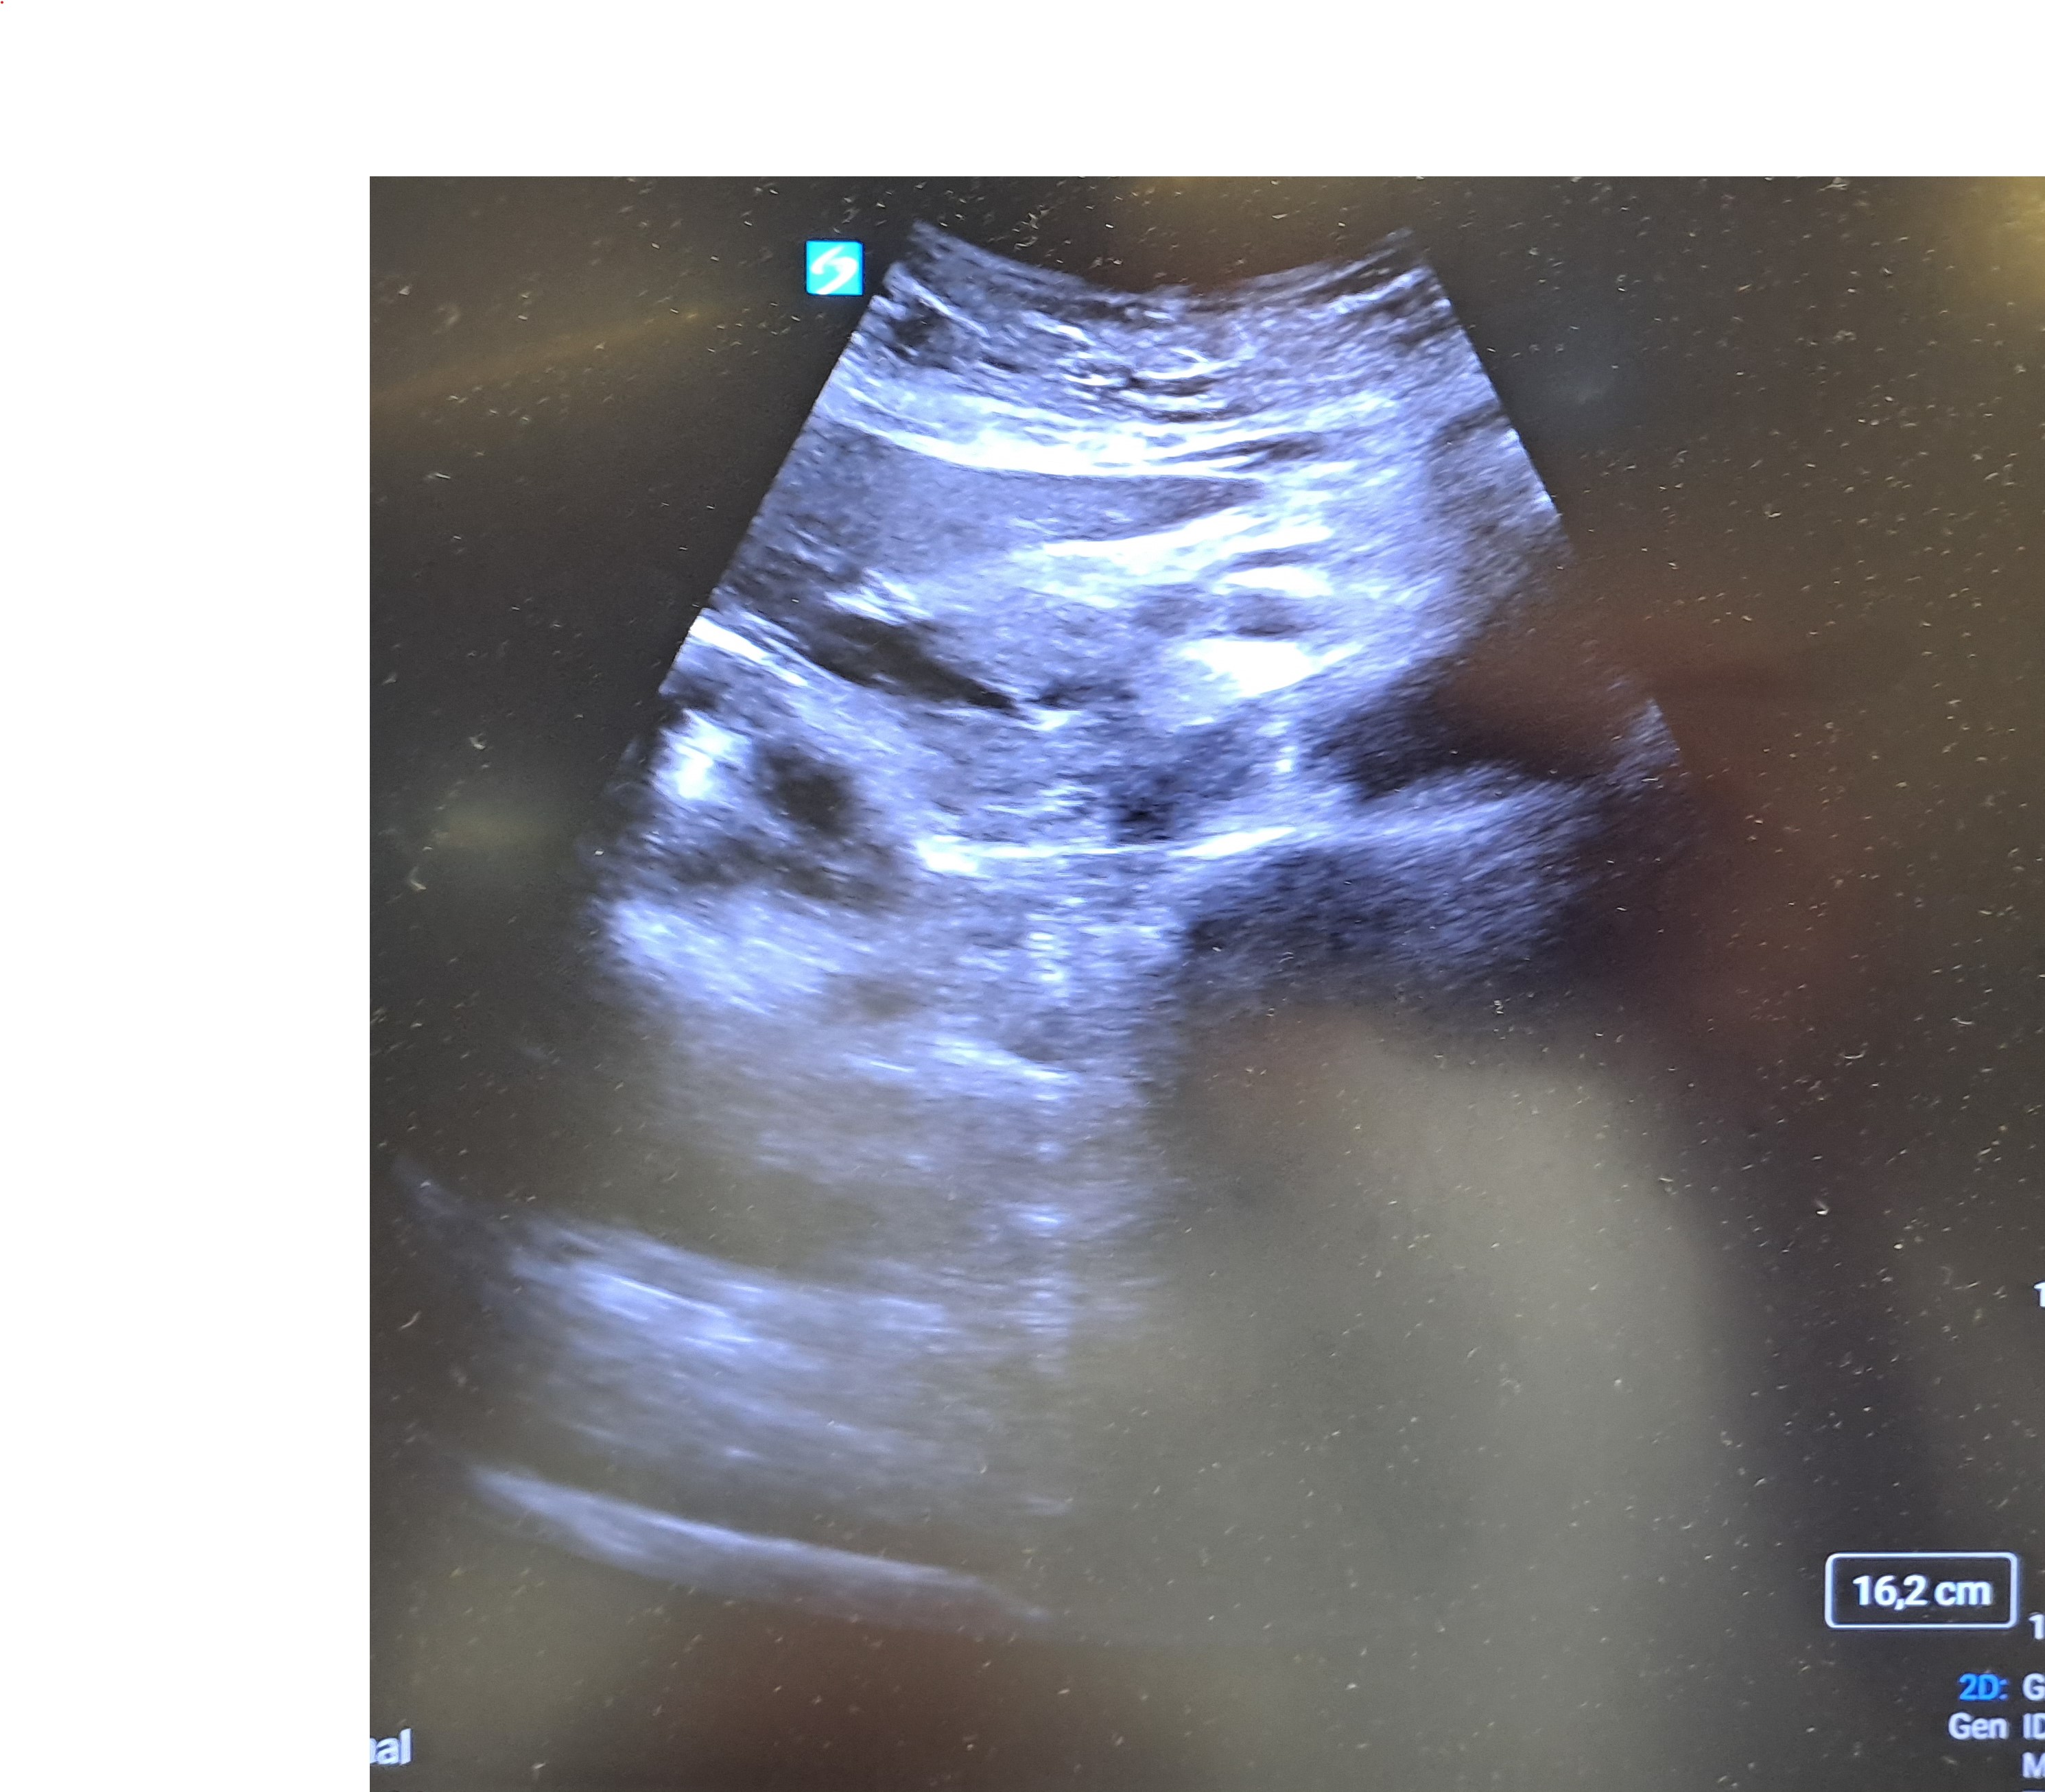

Ecografía abdominal: Hígado de bordes lisos y homogéneos, no lesiones ocupantes de espacio. Vesícula biliar no dilatada, no engrosamiento de paredes. Presencia de múltiples lesiones anecoecogénicas redondeadas en cabeza de páncreas, la mayor de unos 5cm de diámetro, no se objetivan lesiones en cuerpo y no se visualiza cola del páncreas. Riñones: no alteraciones en la ecogenicidad o tamaño.